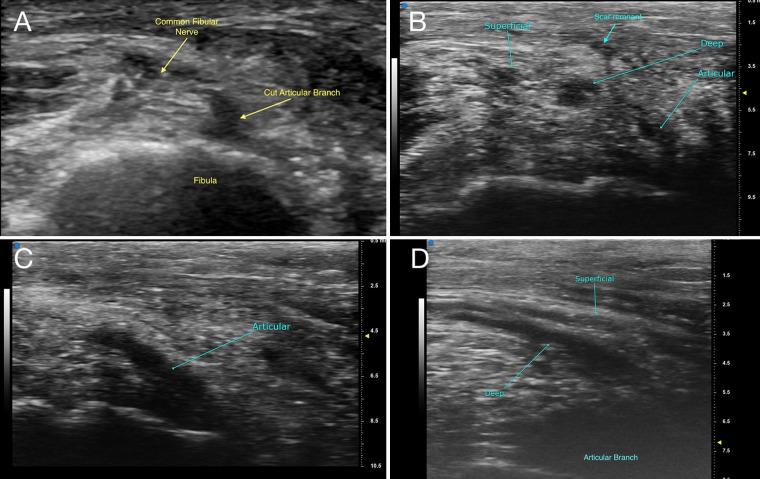

Foot drop is a common complaint with a broad differential diagnosis making imaging a key part of the diagnostic workup. The authors present a patient with an occult peroneal intraneural ganglion cyst who underwent imaging with high-frequency ultrasound (US) and high-resolution magnetic resonance imaging (MRI) to highlight the role of such techniques in cases of peroneal neuropathy.

Intraneural ganglion cysts are emerging as a common cause of common peroneal neuropathy. Imaging with US and MRI is a valuable tool used to illustrate the pertinent anatomy and identify the articular branch joint connection and cyst as part of the surgical planning and definitive management.

Intraneural ganglion cysts can be small or nearly invisible and failure to appreciate the intraneural cyst can lead to symptom or cyst persistence or recurrence. High-resolution modalities can be useful in the diagnosis and surgical planning of difficult cases.